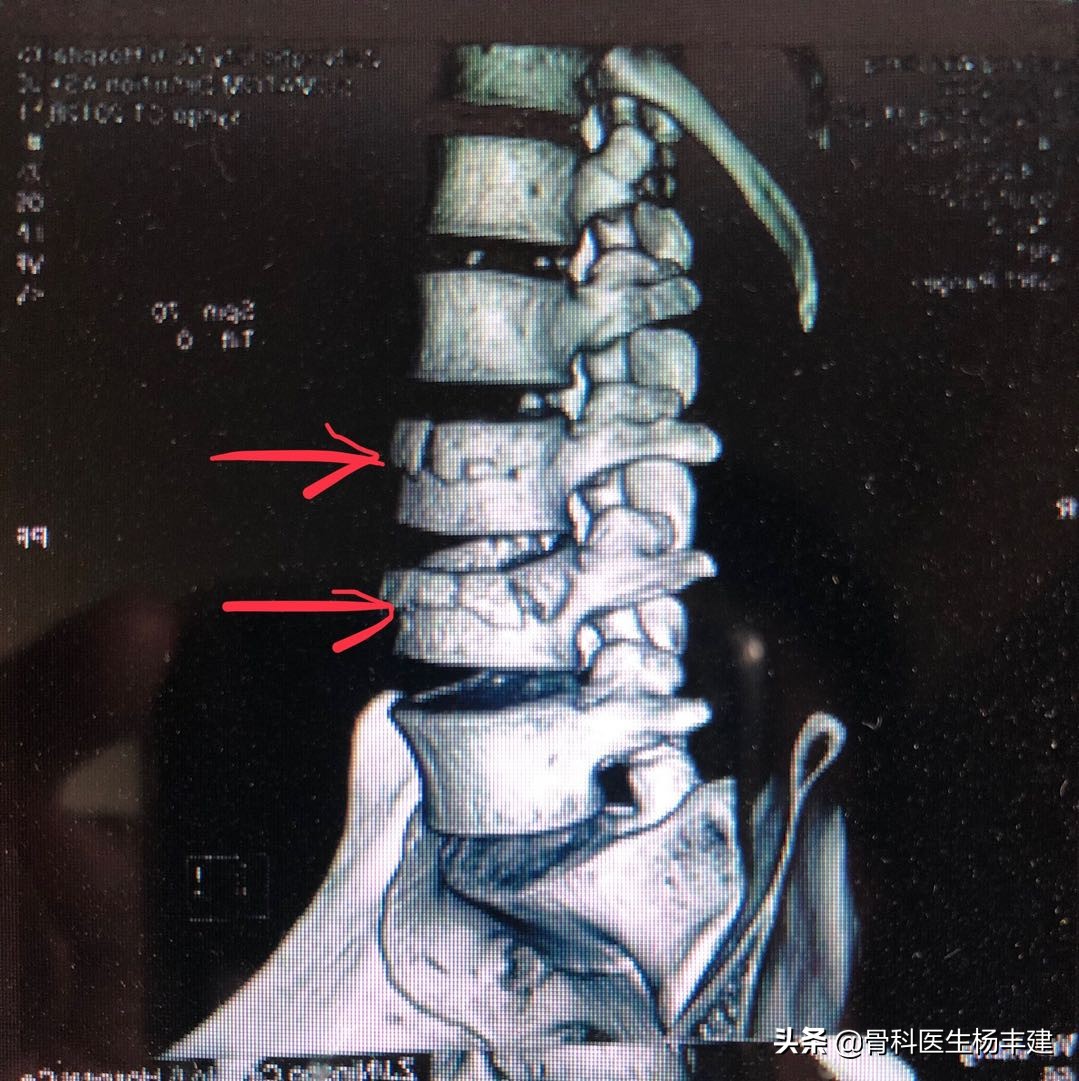

对于皮质变形明显的骨折,CT重建的图像也很清楚,红箭处为两个椎体骨折

kummel病的典型CT表现,脊柱中间出现明显的空腔,无法彻底愈合